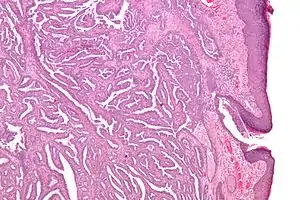

| Micrograph of a nipple adenoma. H&E stain. | |

Once excised, the macroscopic appearance of nipple adenomas is of a poorly defined nodular mass. The microscopic appearance can be quite bizarre, and may be misinterpreted as a carcinoma. Nipple adenomas usually have a rounded outline at low magnification, and at higher magnification can be seen to consist of a haphazardly arranged mass of proliferating tubular structures composed of epithelial and myoepithelial cells within varying amounts of fibrous stroma. The epithelial cells are usually columnar, but the columnar epithelial cells can undergo apocrine or squamous metaplasia. Mitotic figures and necrosis are not commonly seen.[1]